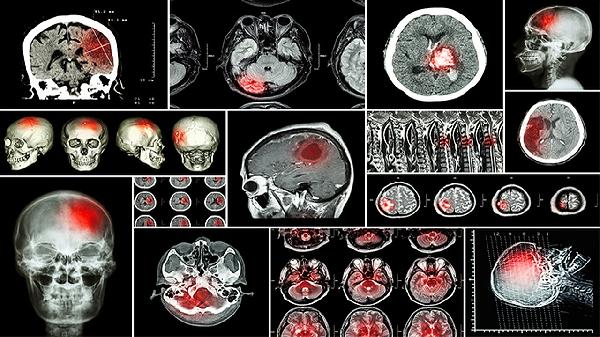

什么是短暂性脑缺血发作 短暂性脑缺血发作3个症状很凶险

短暂性脑缺血发作是脑部血液供应暂时性中断引起的神经功能障碍,通常持续数分钟至1小时,24小时内完全恢复。主要症状包括突发单侧肢体无力、短暂性失语或言语含糊、单眼视力突然丧失。虽然症状可逆,但属于脑梗死高危预警信号,建议立即就医。